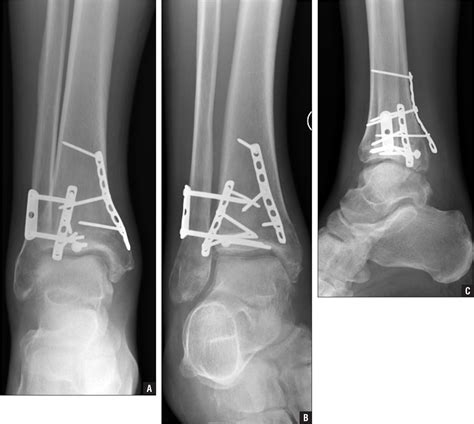

• Imaging Tests: X-rays, MRI, or bone scans may be ordered to visualize the fracture and determine its severity.

X-rays are often the first line of imaging, but they may not always show stress fractures, especially in the early stages. MRI and bone scans are more sensitive and can provide a clearer picture of the fracture.

In severe cases, surgery may be required to stabilize the fracture and promote healing. However, this is relatively rare and is typically reserved for cases where conservative treatments have failed.